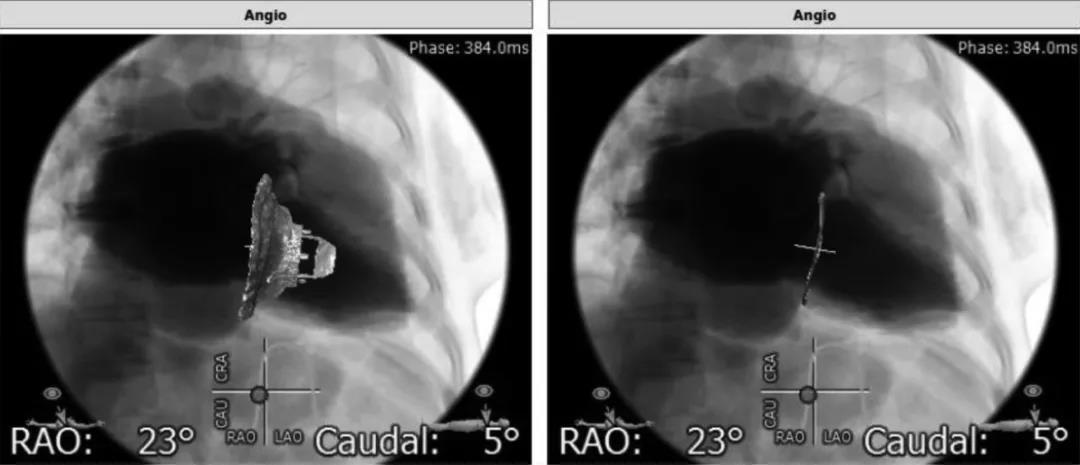

整个手术过程非常顺利,瓣膜置入成功,术后超声和造影都显示瓣膜位置良好,无明显瓣周漏。术中陆方林教授非常耐心地向大家讲解操作的方法和技巧,现场嘉宾也对新型瓣膜表示出浓厚的兴趣和充分的肯定,LuX-Valve®手术国际首秀在术者和嘉宾愉快的讨论过程中圆满成功。

瓣膜植入术后右心室造影